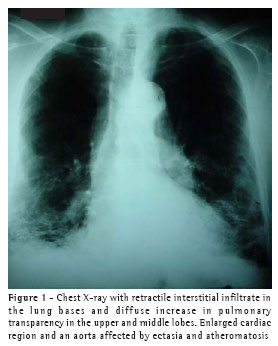

A chest X-ray (Figure 1) showed retractile interstitial infiltrate in the lung bases, rectification of the hemidiaphragm with ill-defined borders, diffuse increase in pulmonary transparency in the upper and middle lobes, and enlarged cardiac image, as well as an aorta affected by ectasia and atheromatosis.